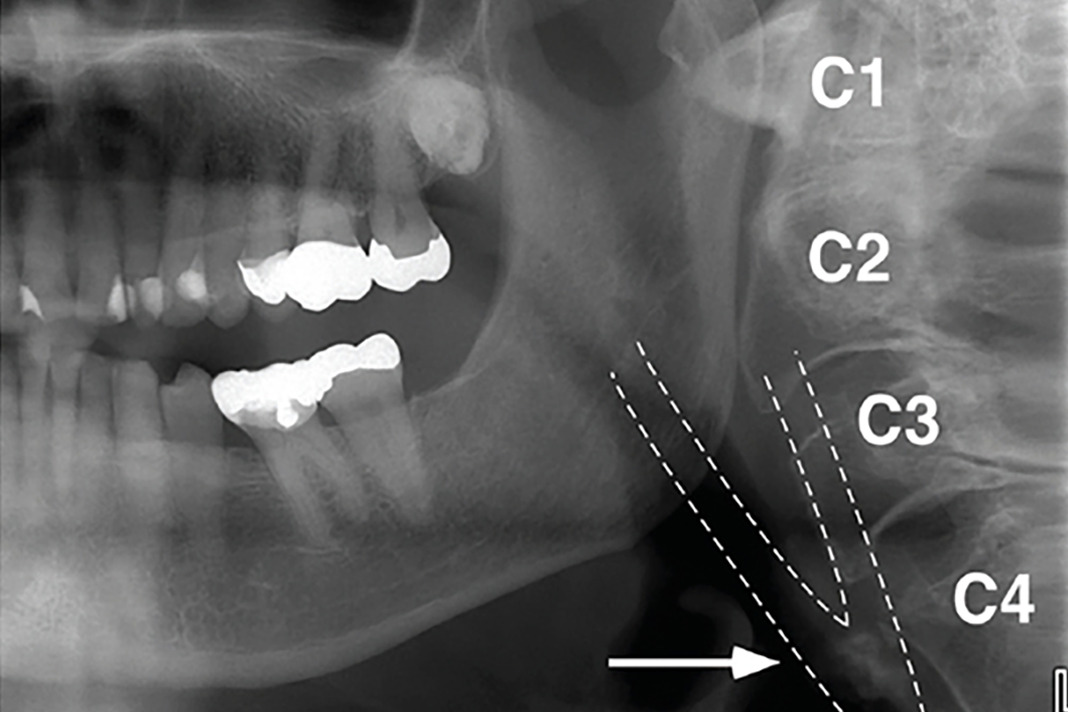

Lateral cervical Xray film in the neutral positions. HMDn, the Panoramic X-Ray Thyroid Collar Do not use a thyroid collar. The thyroid gland is one of. The recently updated national council on radiation protection and measurement radiation protection in dentistry and oral and. Wearing a thyroid collar was helpful when the direct digital panoramic imaging. The recently updated national council on radiation protection and measurement radiation protection in dentistry and oral and. Thyroid gland. Panoramic X-Ray Thyroid Collar.